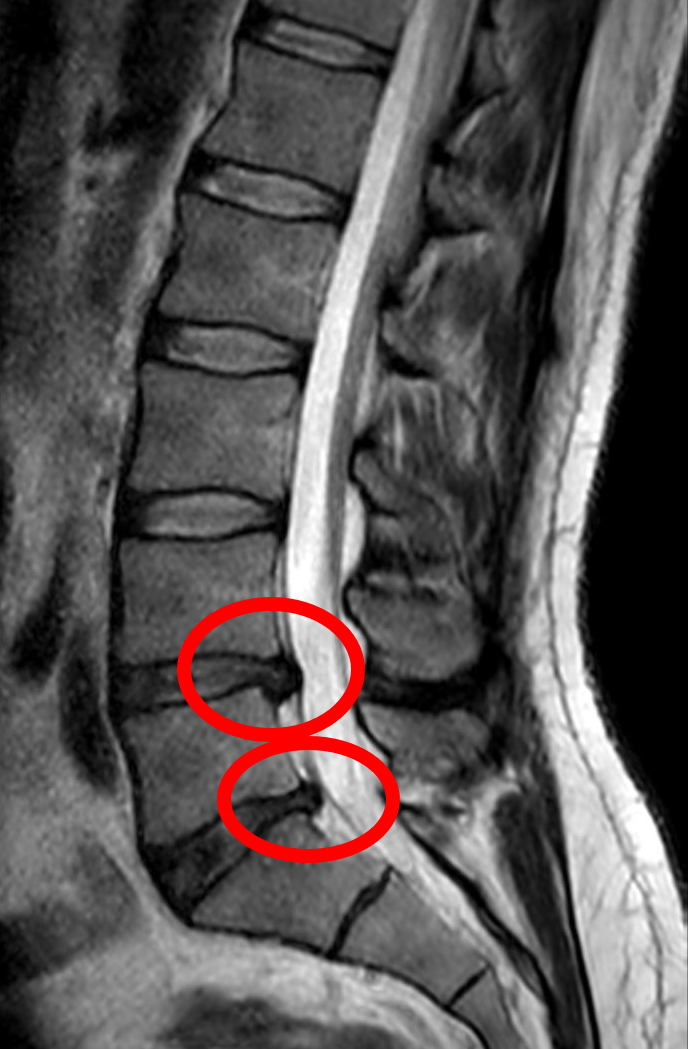

Injuries and Disc Degeneration

Injuries to the spine, especially to the discs, can drastically affect this daily height fluctuation. Conditions like herniated discs or degenerative disc disease make it harder for the discs to rehydrate at night. People with chronic back problems may see less of a morning height boost or even experience constant pain. Protecting your spine from injuries is crucial if you want to keep enjoying your daily growth spurt.